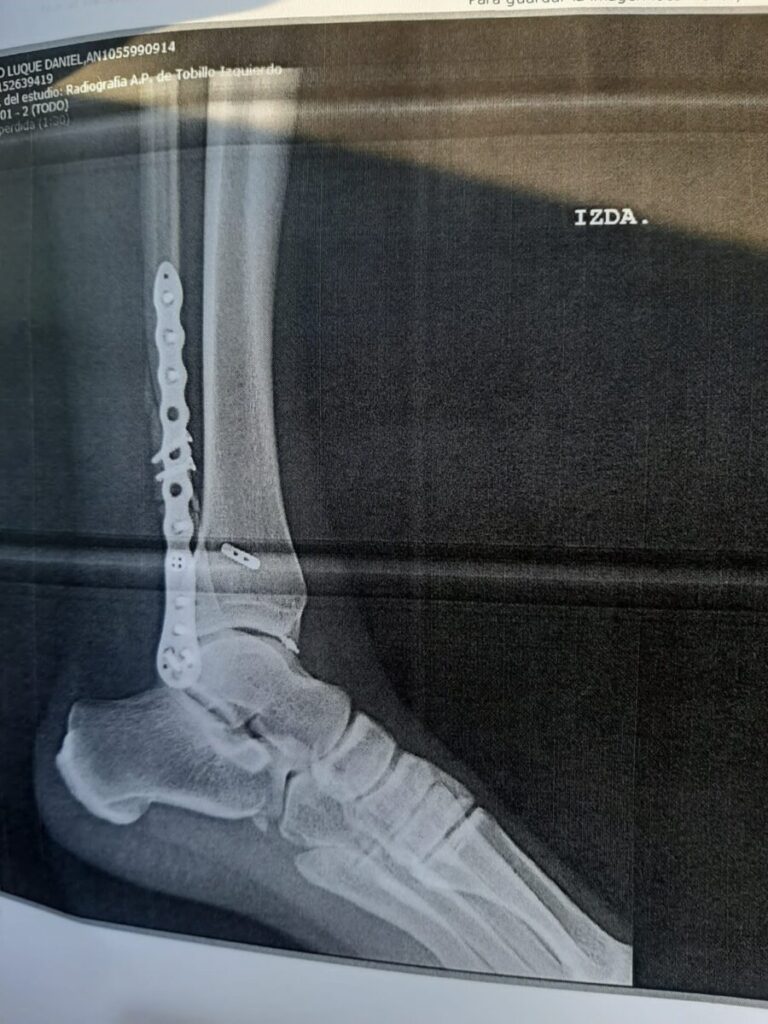

Durante la revisión, los facultativos han hecho unas radiografías a Daniel Luque -que se adjuntan- donde se aprecia abiertamente el alcance de la grave lesión del torero de Gerena. La evolución es buena si bien se observa cómo tiene todo el peroné lleno de tornillos y placas de unión, colocadas durante la intervención quirúrgica a la que fue sometido en Sevilla el pasado 13 de agosto.